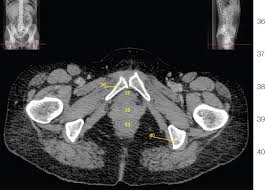

Mri anatomy of the male pelvis and pelvic floor in multiple patients aged 50 years or older. Presentation1.pptx, ct normal anatomy of the abdomen and pelvis. Anatomy ct axial abdomen and pelvis male male abdomen and pelvis ct scan form no 1. Int/ext obliques transversus spine muscles: Muscles of the pelvis that cross the lumbosacral joint to attach onto the trunk were described in. Ct and some mr imagings of nine patients who received irradiation to the pelvis and of eleven patients who received transarterial infusion for urinary bladder carcinoma were studied about the anterior and posterior attachment sites of the coccygeus muscle, the sacrouterine ligament and the lateral. Pelvic floor anatomy is complex and is being unraveled by means of magnetic resonance mr imaging. Anatomy ct axial abdomen and pelvis male from 3.bp.blogspot.com the lateral superficial muscles, the transversus and external and internal oblique muscles, originate on the rib cage and on the pelvis (iliac crest and inguinal ligament) and are attached to the anterior and posterior layers of the sheath of the rectus. Volume rendered display, ct of the pelvis • the external surface of the iliac blade is the attachment site for the gluteus medius and minimus muscles. Functional anatomy of the male pelvic floor online course: The medial thigh muscles are responsible for the adduction (movement of a body part toward the body's midline) of the leg. Schau dir angebote von ‪muscle anatomy‬ auf ebay an. Axial section through male bladder.

Ct and some mr imagings of nine patients who received irradiation to the pelvis and of eleven patients who received transarterial infusion for urinary bladder carcinoma were studied about the anterior and posterior attachment sites of the coccygeus muscle, the sacrouterine ligament and the lateral. They form a large sheet of skeletal muscle that is thicker in some areas than in others. Int/ext obliques transversus spine muscles: The pelvic floor muscles provide foundational support for the intestines and bladder. 48 adductor longus muscle this muscle is the most. 15 liver 16 oesophagus 17 stomach. Anatomy ct axial abdomen and pelvis male male abdomen and pelvis ct scan form no 1. Volume rendered display, ct of the pelvis • the external surface of the iliac blade is the attachment site for the gluteus medius and minimus muscles. Weak adductor muscles may cause knee instability and adductor strain (2). Muscles that attach from the pelvis to the trunk and cross the lumbosacral joint muscles that attach from the pelvis to the thigh/leg and cross the hip joint pelvic floor muscles that are located wholly within the pelvis The muscles of the pelvic floor are collectively referred to as the levator ani and coccygeus muscles. Quadratus lumborum anatomy radiographs ct protocols pelvic ring fx ap force lateral. An important group of muscles in the pelvis is the pelvic floor.

This mri male pelvis axial cross sectional anatomy tool is absolutely free to use anatomy muscles pelvis. Ct anatomy of the pelvis.